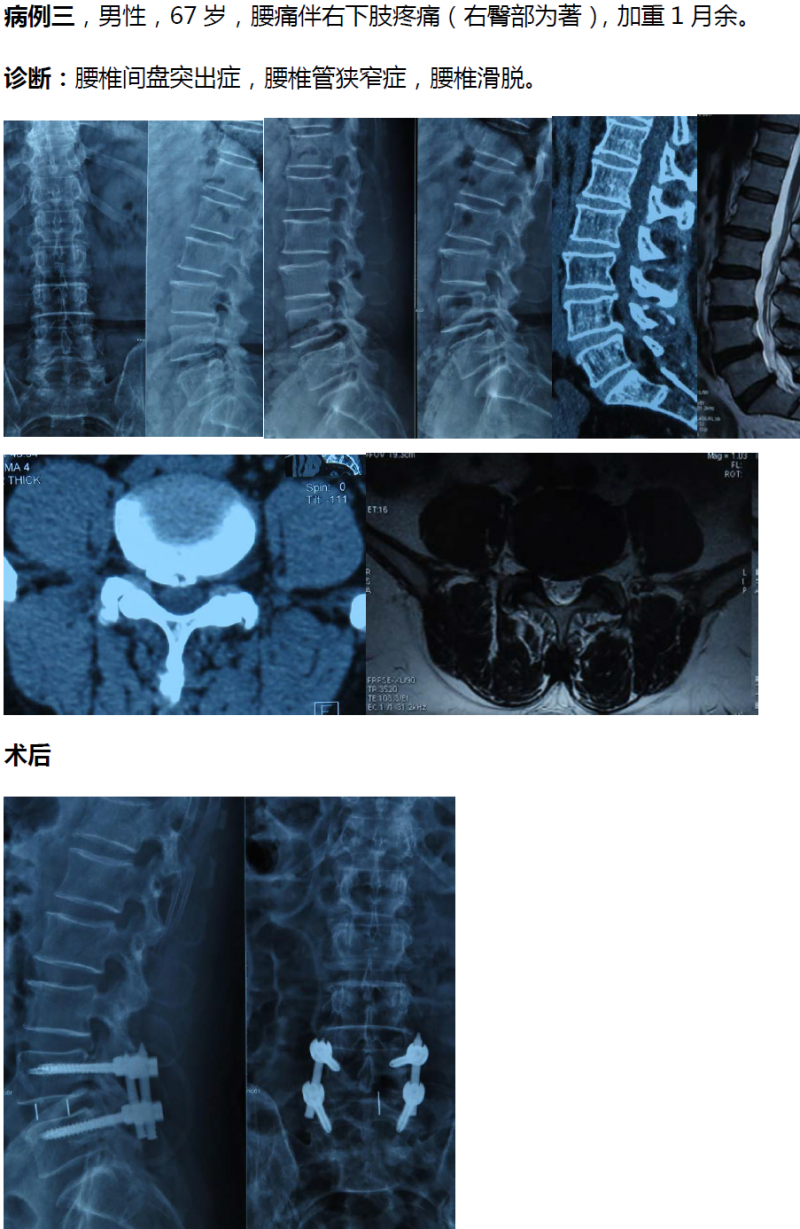

总的来说,单边双通道镜下融合技术和LUSTA大通道镜下融合技术对于解决腰椎间盘突出症、腰椎管狭窄症合并腰椎不稳以及Ⅱ°以内腰椎滑脱均有显著疗效,两种技术应该平行发展,两架马车应并驾齐驱共同前进。

病例分享:(滑动查看)